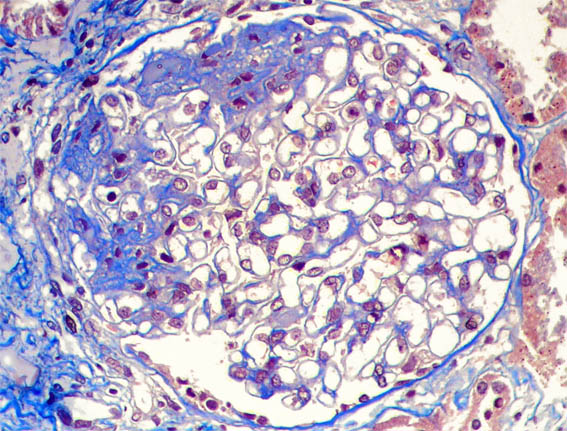

Tricrómico de Masson, X400.

Figura 6.